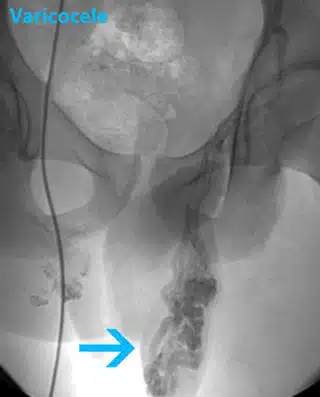

3. Percutaneous embolization varicocelectomy

This outpatient procedure is done under local anesthesia. This method provides the least invasive varicocelectomy. The doctor inserts a tube into a vein in the groin. He passes a catheter through the tube and views the enlarged veins on the monitor by a camera that is attached to the catheter. He releases coils or solution that makes scarring to create a blockage in the testicular veins and repair the varicocele. The relatively noninvasive nature and preservation of the testicular artery are the advantages of percutaneous embolization